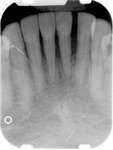

After all dental infections have been removed, patients can initiate IV therapy. Dentists should follow-up regularly with these patients during their bisphosphonate therapy, preferably once a month. After patients are off bisphosphonate therapy for 2 months, their radiograph series should be updated. The radiographs should be viewed for signs of sclerosis of the lamina dura or widening of the periodontal ligament because these are usually the first places where signs of bisphosphonate toxicity and osteonecrosis can be seen.19

Under the sextant approach, one quadrant is treated and the patient is left to heal for 2 months before proceeding to any additional quadrants. While the patient heals, a 10-day course of antibiotics and 2 months of twice-daily chlorhexidine rinsing may be prescribed. Figure 4 shows a patient who was taking oral bisphosphonates for 3 years and was treated with the sextant approach. As seen in the radiograph, the patient has one molar in the lower right quadrant. This tooth was extracted and the patient was given 2 months to heal (Figure 5 and Figure 6).The patient was placed on antibiotics and chlorhexidine rinse. After 2 months, no signs of BRONJ were observed, and the anterior teeth were scheduled for extraction. They were extracted as atraumatically as possible, and the site was sutured (Figure 7 and Figure 8).The patient then was given another 2 months to heal, following the previous protocol.After 2 months of healing, no BRONJ was observed (Figure 9).

Figure 4 Radiograph of oral bisphosphonate user. Figure 5 and Figure 6 After 2 months of healing, the lower right quadrant showed no signs of BRONJ and the anterior teeth were scheduled for extraction. Figure 6

Figure 11 The radiograph shows 80% bone loss.